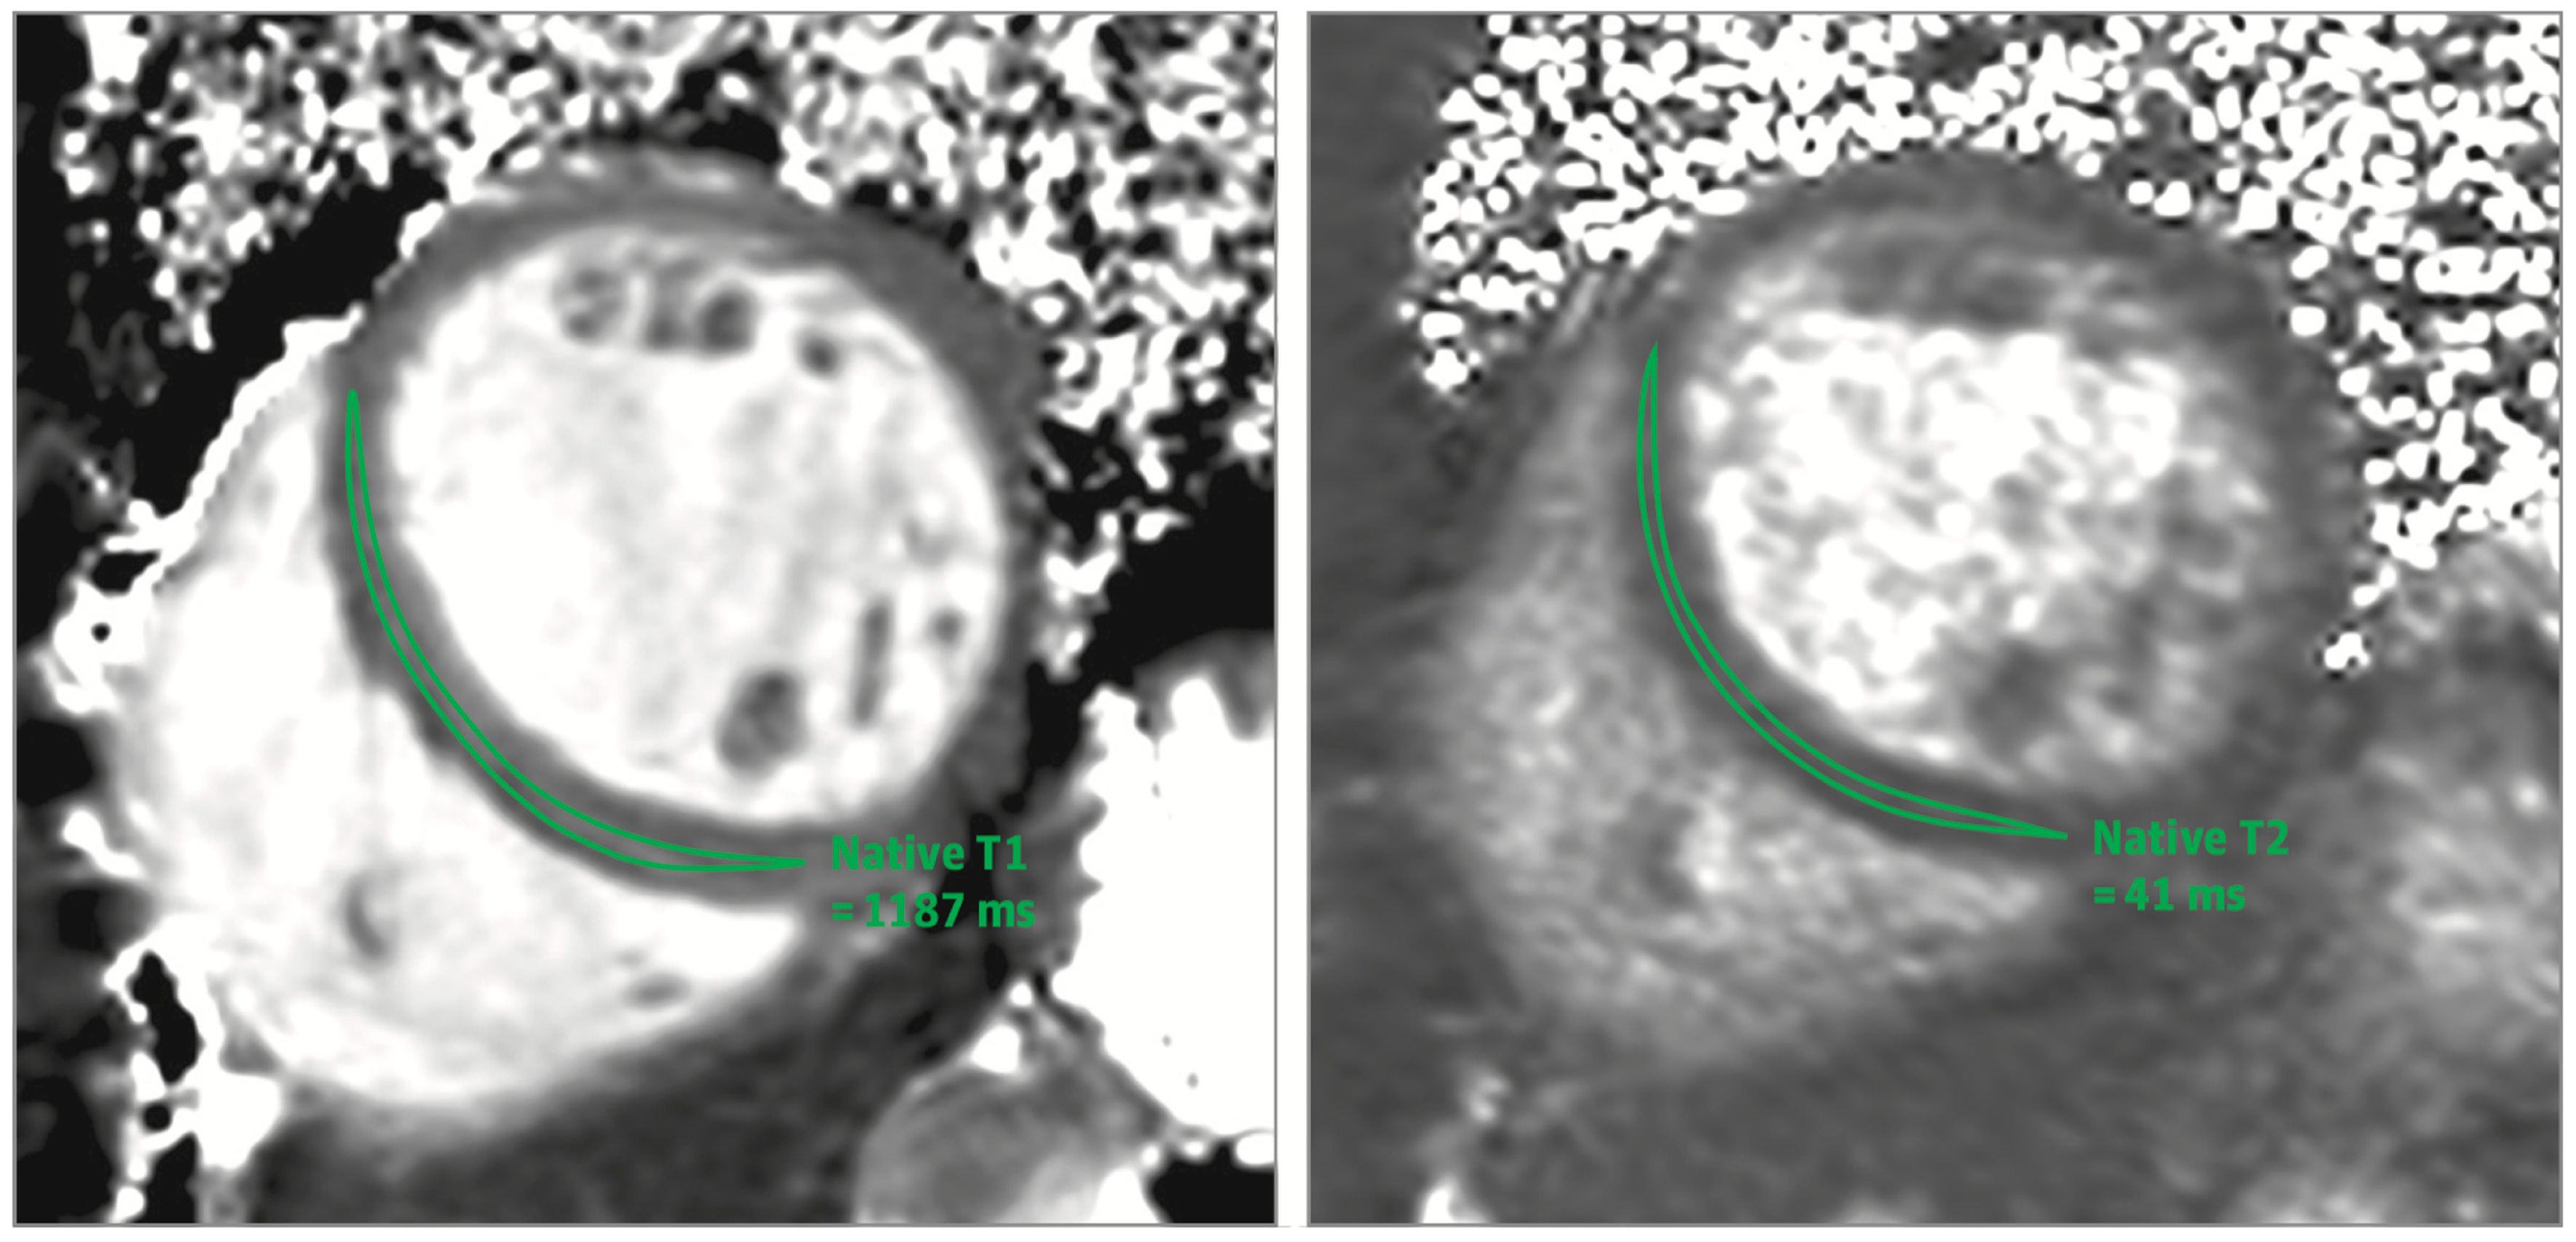

3.2.1. Myocardial Edema

3.2.2. Hyperemia and Extracellular Expansion